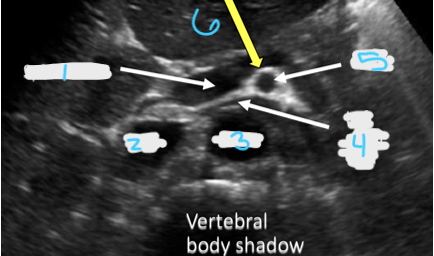

<p>In this transverse view, what is #1?</p>

In this transverse view, what is #1?

<p>In this transverse view, what is #2?</p>

In this transverse view, what is #2?

Common Hepatic Artery

<p>In this transverse view, what is #3?</p>

In this transverse view, what is #3?

<p>In this transverse view, what is #4?</p>

In this transverse view, what is #4?

<p>In this transverse view, what is #5?</p>

In this transverse view, what is #5?

<p>In this transverse view, what is #6?</p>

In this transverse view, what is #6?